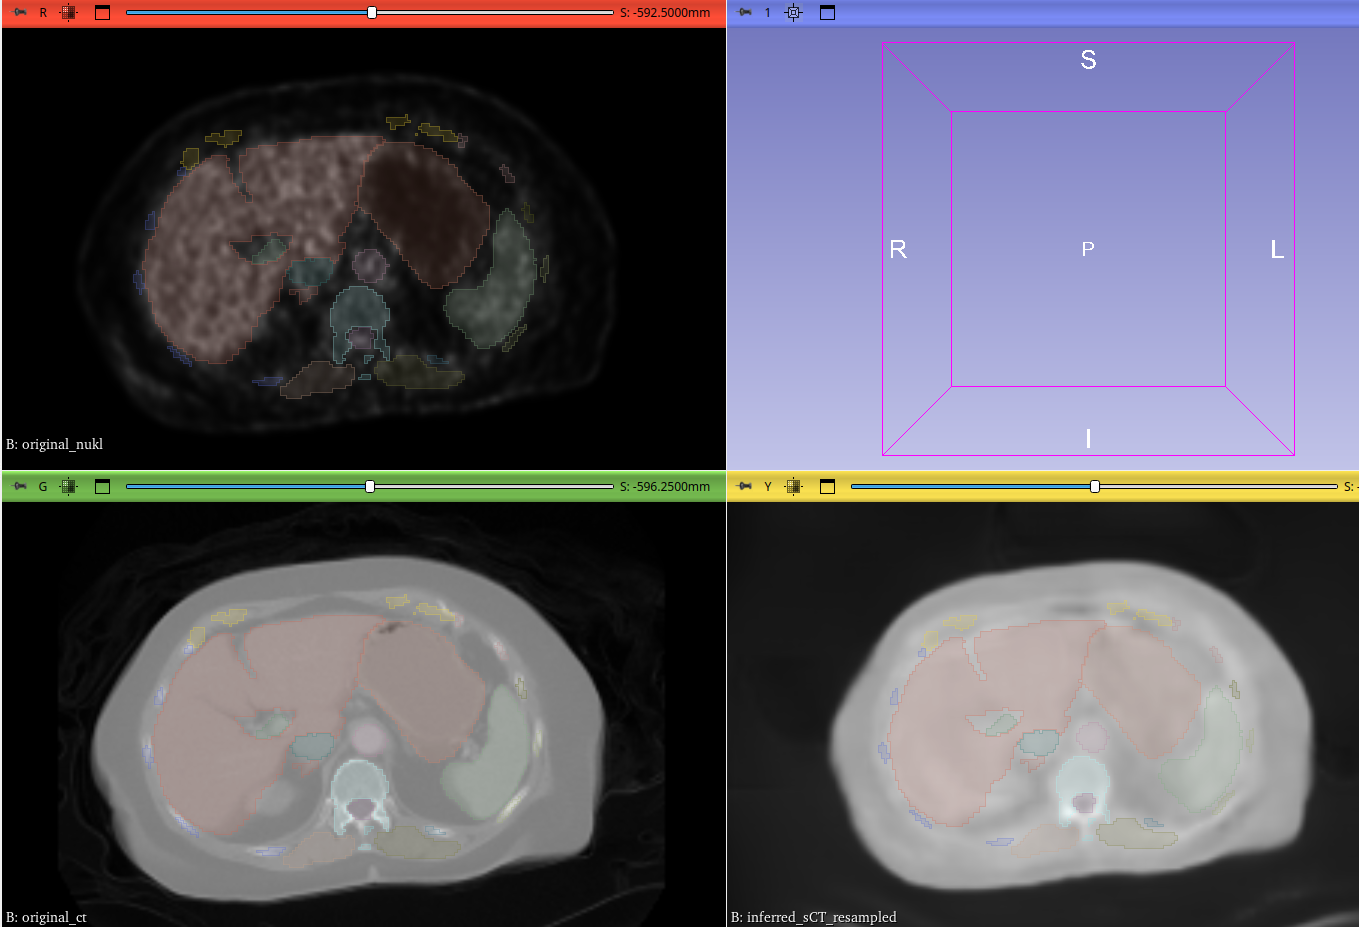

Visualizing the Results

PET vs. Original CT vs. Synthetic CT

This comparison highlights the anatomical accuracy of our synthetic CT (right), which closely mirrors the ground truth of the original CT (middle) while retaining the functional context from the PET scan (left).

Comparison of PET, original CT, and synthetic CT scans